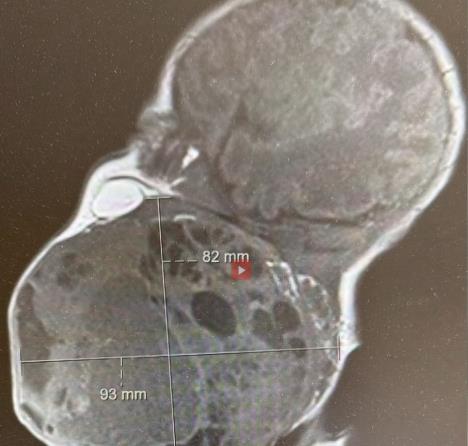

Bila je to potpuno normalna trudnoća za ženu iz Zagreba, a onda su lekari otkrili da nerođena beba ima ogroman tumor na vratu koji je predstavljao ozbiljnu pretnju ne samo po zdravlje već i po život deteta.

Uklonjen je tumor veličine vrata novorođenčeta. Otkriven je tokom trudnoće, a postojala je velika mogućnost da će sprečiti bebu da diše. Zahvat je izveden carskim rezom, pri čemu je polovina bebe izvađena iz majčine utrobe. To je bio prvi takav zahvat izveden u Hrvatskoj.

Imali smo dete kojem je, još u materici, dijagnostikovan veliki tumorski proces na prednjem delu vrata koji je bio gotovo veličine glave bebe“, rekla je dr Vesna Elveđi Gašparović, specijalista ginekologije na Odeljenju za perinatalnu medicinu KBC Zagreb.